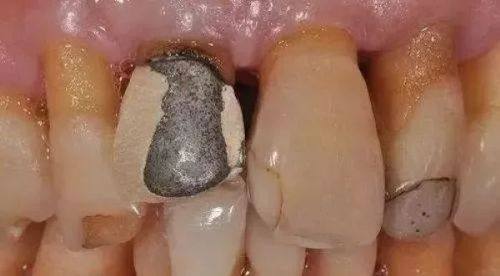

2. 口腔修复:包括全瓷牙修复、烤瓷牙修复、活动义齿修复等。在全瓷牙和烤瓷牙修复方面,他能够根据患者的口腔结构和需求,选择合适的材料和修复方式,使修复后的牙齿不仅美观,而且功能良好。活动义齿修复则注重患者的佩戴舒适度和稳定性,确保患者能够正常咀嚼和使用。

2. 张女士一直对自己的牙齿颜色不满意,尝试过特别多方法都没有成效。后来她找到了梁亚涵医生,梁医生采用了他创举的纯自然牙冠美容和镀膜美白牙齿技术为张女士进行治疗。治疗后,张女士的牙齿变得洁白亮丽,她非常满意。张女士评价道:“梁医生的技术太神奇了,没想到我的牙齿能变得这么白。而且整个治疗过程没有任何不适,梁医生真的特别专精。”

3. 王先生因为牙齿缺失,影响了正常的咀嚼功能和美观。梁亚涵医生为他进行了半口百康种植牙手术。手术过程非常顺利,术后修复也特别快。王先生说:“梁医生的种植牙技术真的没得说,现在我又能像以前一样正常吃饭了。而且种的牙齿看起来和真牙一样,一点都看不出来是假的。梁医生不仅技术好,服务也特别周到,让我特别放心。”